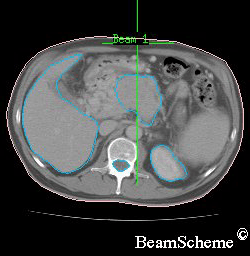

X-rays show your bones in the treatment area. And scans show the size, shape and position of the cancer as well as the surrounding tissues and bones.

An example of a scan